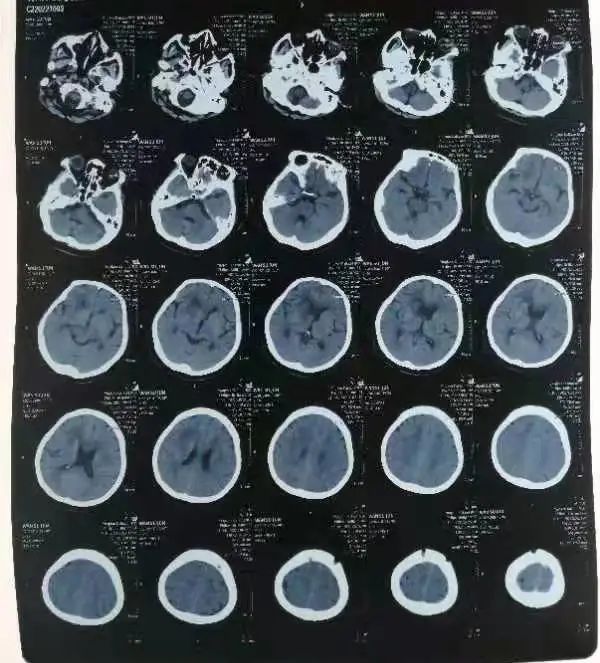

经过前期充分的准备,手术很快开始。术中,吕松林主任凭借丰富经验,顺利将脑室引流管深入到了血肿关键位置。术后,在反复比对斟酌下,吕主任带领科室医护团队多次成功溶血后,顺利打开脑室循环通路。神经外科护理团队也紧跟治疗节奏,全程加强护理及预防,采用了多种护理方式纠正电解质紊乱、改善微循环,李奶奶终于转危为安。

(术后)

(出院前)